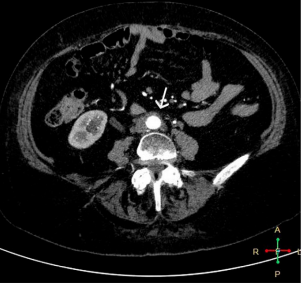

MDCT with contrast was performed, which reported a slight decrease in the retroperitoneal image (Figure 1 and 2), so it was decided to continue with corticosteroid treatment and outpatient follow-up to schedule surgery with biopsy.

Figure 1 MDCT with intravenous contrast, arterial phase, axial view. There is evidence of dense soft tissue formation surrounding both iliac arteries.